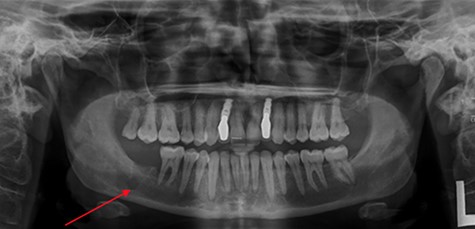

At her OMFS appointment, the consultant was concerned by the abnormal appearance of the extraction site intraorally, combined with the evolving systemic symptoms (Figs 2–4). Urgent magnetic resonance imaging (MRI) head and neck (Figs 5 and 6) and computerized topography (CT) mandible scans were requested and completed in an extremely short time frame.

OPG taken on admission to RDH. Note: LR7 has been extracted and there is a patch of radiolucency inferior to LR7/8.